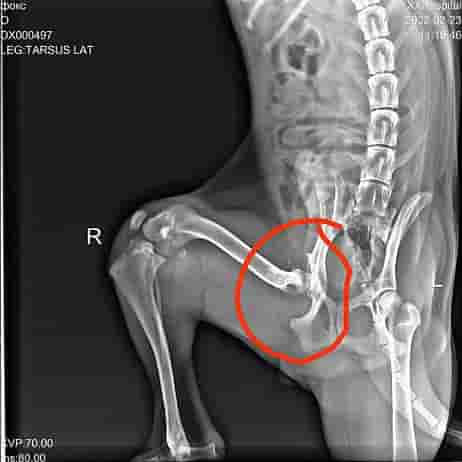

И вот у Фокса новая страничка в жизни и она начинается с испытания. Проблема с тазобедренным суставом. Пока он ещё молодой и идёт рост нужно принимать решение, потом при закостенении сустава это будут сильные боли.

Сделали рентген, проконсультировались с несколькими хирургами и приняли решение. 19 марта 2022 года будет операция.

Делать будем у нашего любимого хирурга Игоря Евгеньевича из клиники Дельта в Бирюлёво, он не раз уже собирал, как говориться, наших бедняг по частям и они сейчас ходят на своих лапках.